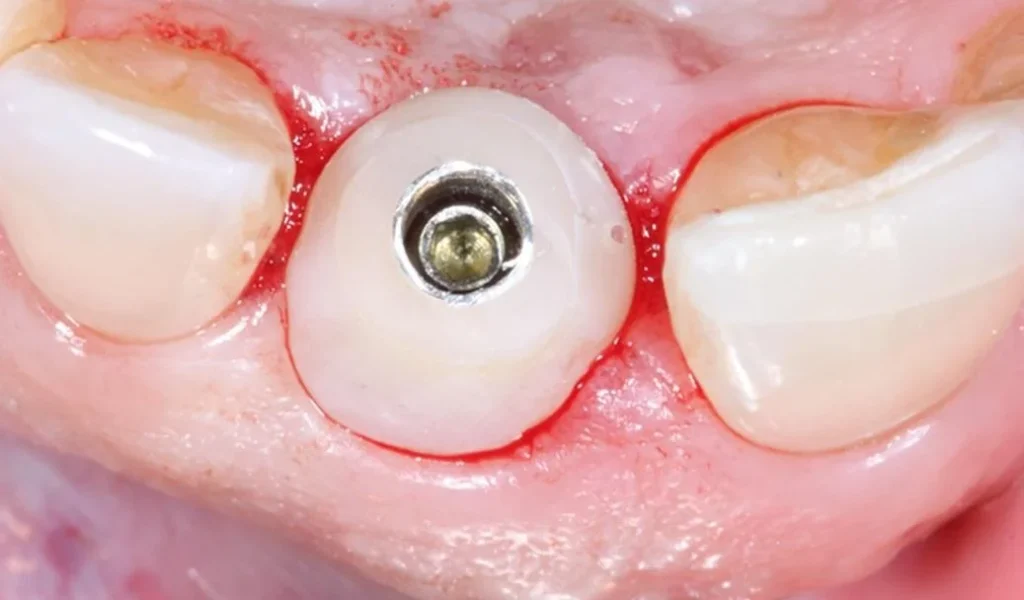

Feature 2: Reconstruction of gingiva and periodontal tissues according to anatomical standards using Healing Customized.

Periodontal tissue surrounding the tooth is extremely important. Biologically, periodontal tissue connects to the tooth through ligaments and junctional epithelium, forming a biological barrier that prevents bacteria from penetrating deeper. Aesthetically, periodontal tissue creates soft curved contours (known as pink aesthetics), contributing to the uniqueness of each person’s smile.

When a tooth is lost, the surrounding periodontal tissue collapses. With older methods using prefabricated abutments, it is very difficult to regenerate periodontal tissue.

With the personalized implant solution, the healing abutment is custom manufactured by simulating the ideal periodontal morphology for each tooth and each patient. Regenerating periodontal tissue according to anatomical standards helps future implant teeth appear more aesthetic, more biological, and more natural in function.

First aesthetic advantage: Optimal gingival and periodontal aesthetics.

Using Healing Customized to shape and reconstruct periodontal tissue, together with Customized Abutment for contouring, allows the personalized implant tooth to have gingival contours that mimic natural teeth, providing superior “pink aesthetics” compared to traditional implant restorations.